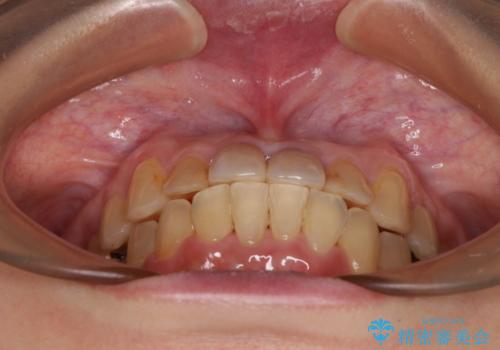

舌の突出癖により治療期間中に開咬となり、治療が長引きましたが、口元も治療前よりも引っ込めることができ、すっきりとした仕上がりとなりました。

気になっていた前歯の変色も、矯正治療後にオールセラミッククラウンにて補綴治療を行うこととしました。